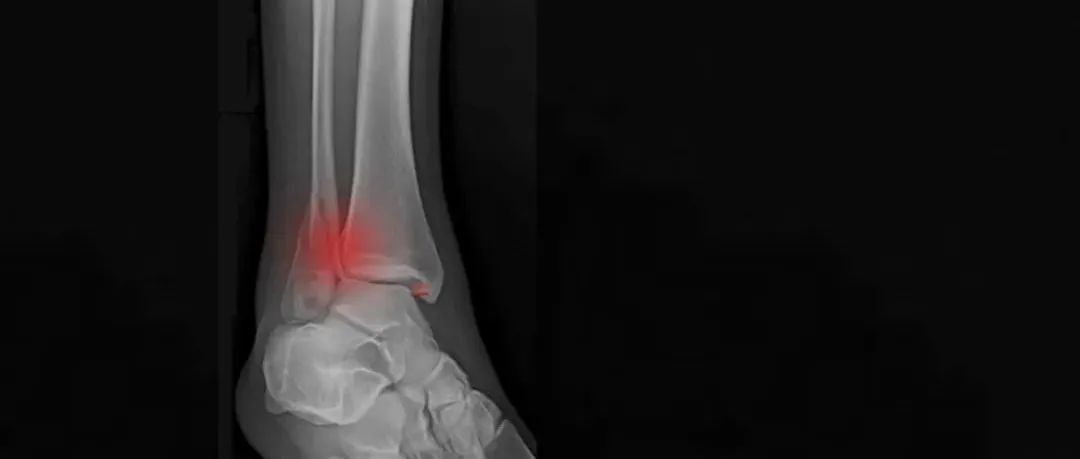

跟骨骨折常见并发症——外侧撞击综合症

今日导读跟骨骨折作为足部骨折中最常见的一种骨折类型,具有发生率较高、具有一定的性别分布特点(男性多于女性)、并且年龄分布以中青年为主,因此会带来深远的社会经济影响。而大多数跟骨骨折为关节内骨折,因此手术治疗成了大多数跟骨骨折的必要手段,但是跟骨骨折术后带来的并发症较多,其中一项即是跟骨的外侧撞击综合症。跟骨骨折术后外侧撞击的原因如果要明确跟骨骨折术后外侧撞击综合症形成的原因,对于跟骨外侧的解剖结构,跟骨骨折的形成机制、以及手术入路、内固定装置都必须要有一个全面的了解。...